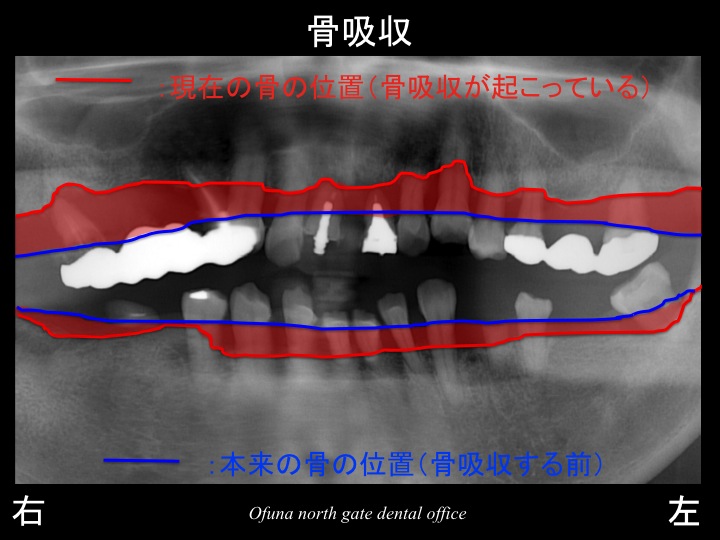

いつものように 骨吸収の状態を分かりやすくするために

骨吸収の状態を線で書いたのが以下のレントゲンになります。

青線が骨吸収を起こす前の骨の位置です。

赤線は、現在の骨の位置です。

さらに分かりやすくするために 骨吸収部位を赤色の領域で表しします。

骨吸収が非常に大きいのが分かります。

多くの歯が初診時にすでにグラグラです。

指で触っても取れそうな歯も多くあります。